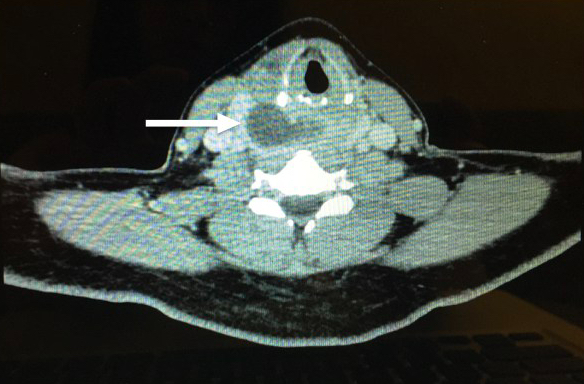

However, CT with IV contrast is the preferred imaging method in these patients. CT can delineate the abscess laterally to determine if there is involvement of the carotid sheath and inferiorly to determine if there is involvement with the mediastinum. Additionally, it aids in planning the surgical approach whether externally or transorally.

Figure 2: Evidence of retropharyngeal abscess on the right side pushing the larynx slightly to the left.